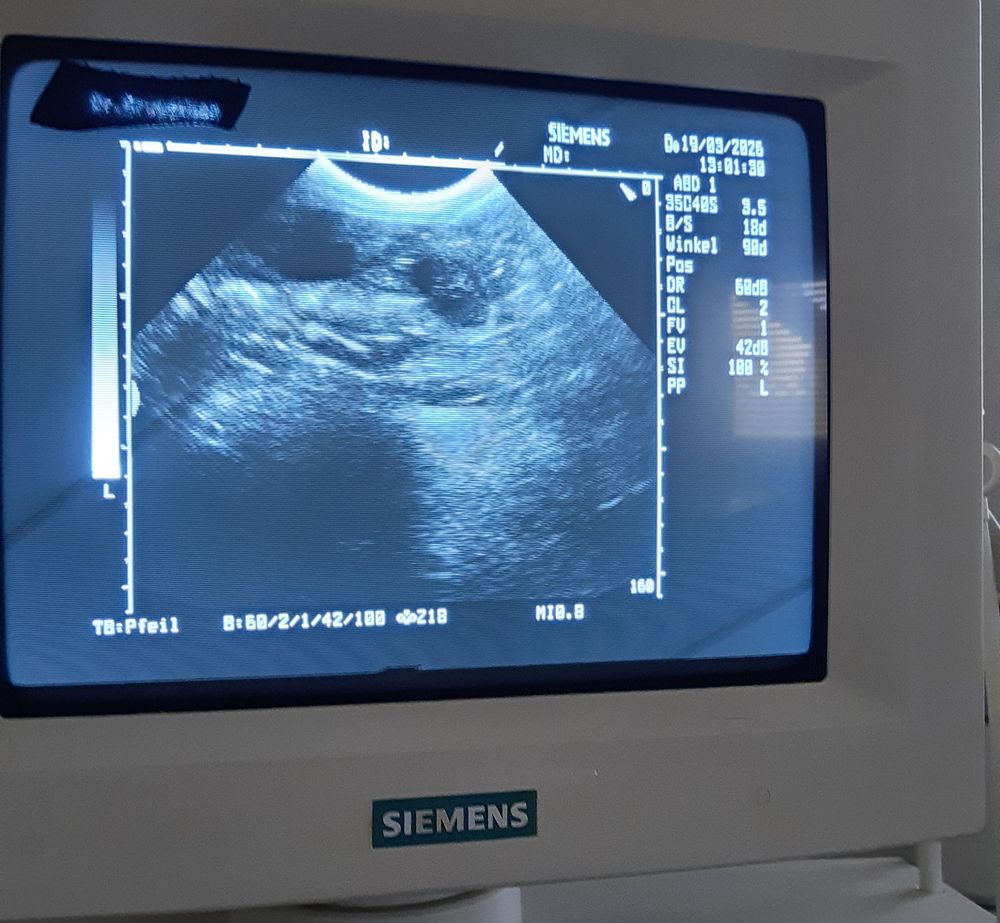

25.03.26 (36. Tag / 6. Woche) Huhu ich schließe mich mal schnell an, Jana hat fertig und Frauli ist noch unten bei der Wäsche, also kann ich euch ein bissel aus meiner Woche erzählen. Mir geht es übrigens super, obwohl mir vor ein paar Tagen schlecht war. Aber das war schnell wieder vorbei. Aber wir laufen viel und ich darf dann immer mit Jana zusammen mit der Schleppi die Gegend unsicher machen. da die jungen Hühner zu doll toben müssen wir an der Schleppi bleiben. Ich natürlich noch aus einem anderen Grund, weil ich immer im Wald schauen muss, was da so los ist. 😉 Meine Maße sind Taille 54 cm und an den Rippen 75 cm noch gleich geblieben. Aber ich bekomme ja nicht so viele Krümel hieß es auf dem Untraschallbild. Lassen wir uns überraschen . LG. eure Mina

20.03.26 (31. Tag 5. Woche) Jiupi jiupi jäh es hat geklappt, Mina ist tragend 😀 Wir freuen uns alle so sehr.